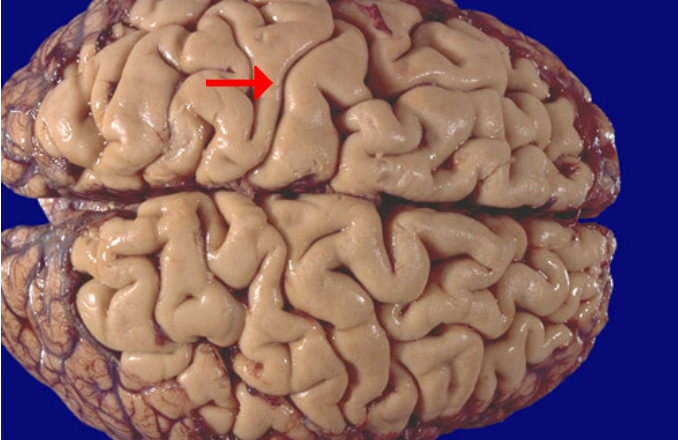

Label this brain region

Precentral gyrus (primary motor cortex)

Label this brain structure

Precentral gyrus (primary motor cortex)

Label this brain structure

Postcentral gyrus